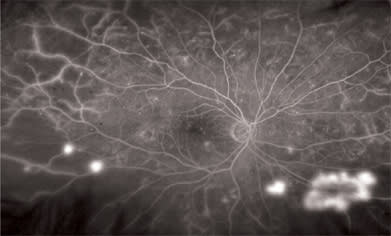

We also have discovered that some patients with diabetic macular edema had more peripheral retinal ischemia than we realized. Evidence suggests these patients may have a reduction in central diabetic macular edema if the peripheral ischemia is ablated. We now take this into consideration as part of our treatment algorithm in patients who have extensive peripheral pathology, shown on widefield imaging. On occasion, we have found patients who have occult peripheral neovascularization by using this advanced imaging technology (Figure 2).

Figure 2. This patient was referred for diabetic macular edema in the right eye. On exam, we saw mild neovascularization of the disc. With an Optos angiogram, multiple areas of peripheral neovascularization were identified as well as later leaking disc neovascularization. The patient underwent uncomplicated photocoagulation, which resulted in regression of the edema and neovascularization. High-resolution macular Optos images were used to guide treatment of the macular disease.